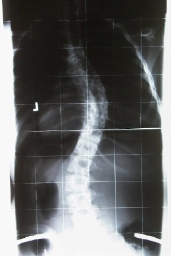

Das kommt raus bei sehr guter Compliance und sehr gutem Korsett, auch bei einer 15-Jährigen:

- Nach 4 Wochen Schroth Reha und ca. 2 Monaten in Korsett mit ca. 70% Korrektur

- kl_4m.k_u.jpg (8.3 KiB) 13976 mal betrachtet

- Skoliose ca. 50°

- kl_50_skoli.jpg (6.07 KiB) 13975 mal betrachtet